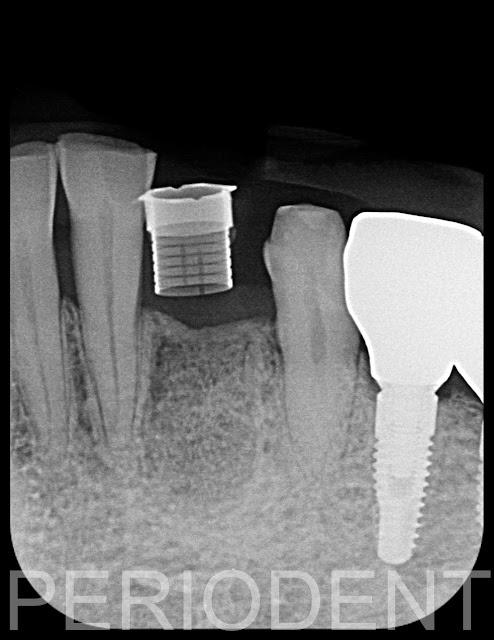

10. 九個月時,口掃及電腦斷層製作植牙手術導板

11. 一年後植牙時,去除過多的骨頭,以得適當的植牙台面高度